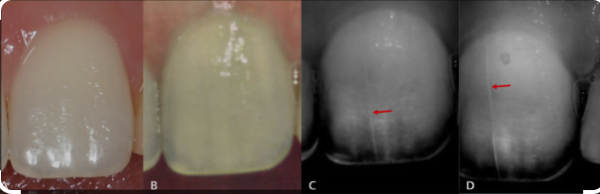

왼쪽 : 교정 전 / 오른쪽 : 교정 후, 치아를 찍는 각도나 불빛에 의해 실금이 다르게 보입니다.

위 경우처럼 교정을 하지 않는 경우에도 실금은 일어날 수 있습니다.

사진상에서 교정 전에 이미 있던 실금이 교정 후에도 그대로 유지되고 있습니다.

아래는 나이와 교정장치 제거가 craze line이 발생하는 빈도와 정도에 영향을 주는지 연구한 한 논문입니다.

강남세브란스 교정과 교수님들께서 지도해 주셨습니다.

치과에 내원하는 모든 환자들의 앞니의 실금을 분석하였습니다.

이들의 나이와 교정치료 여부 등을 조사하였고, 일반 사진, 엑스레이 사진, 투과 스캔 등을 시행하였습니다.

결과적으로 조사한 환자 중 약 50프로에서 이 실금이 발견되었습니다.

20대 이전보다 20대 이후에서 실금이 유의미하게 더 많이 발견되었고, 30대보다 40대에서 더 많이 발견되었습니다.

놀랍게도 교정치료 여부는 실금의 빈도에 영향을 주지 않는다고 나와있습니다.

심지어는 교정장치 종류와도 실금의 빈도와 정도에 상관이 없다는 결과가 나왔습니다.

이러한 결과는 연구 결과의 분석에 있어서 흔히 하는 육안검사가 아닌 엑스레이나 투과 스캔 등을 사용하였기 때문에 그 정도가 과하게 판별되어 교정장치와의 연관성이 줄어든 것으로 보입니다.